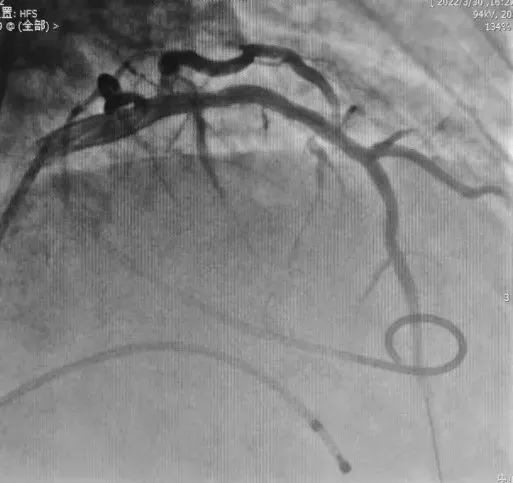

术后

术后造影效果

手术后,患者左室压力与主动脉窦部压力阶差由术前的70mmHg降至5mmHg,流出道流速由3.8m/s降至1.3m/s,成功减轻梗阻,为患者解决了最大的问题,降低了猝死风险。